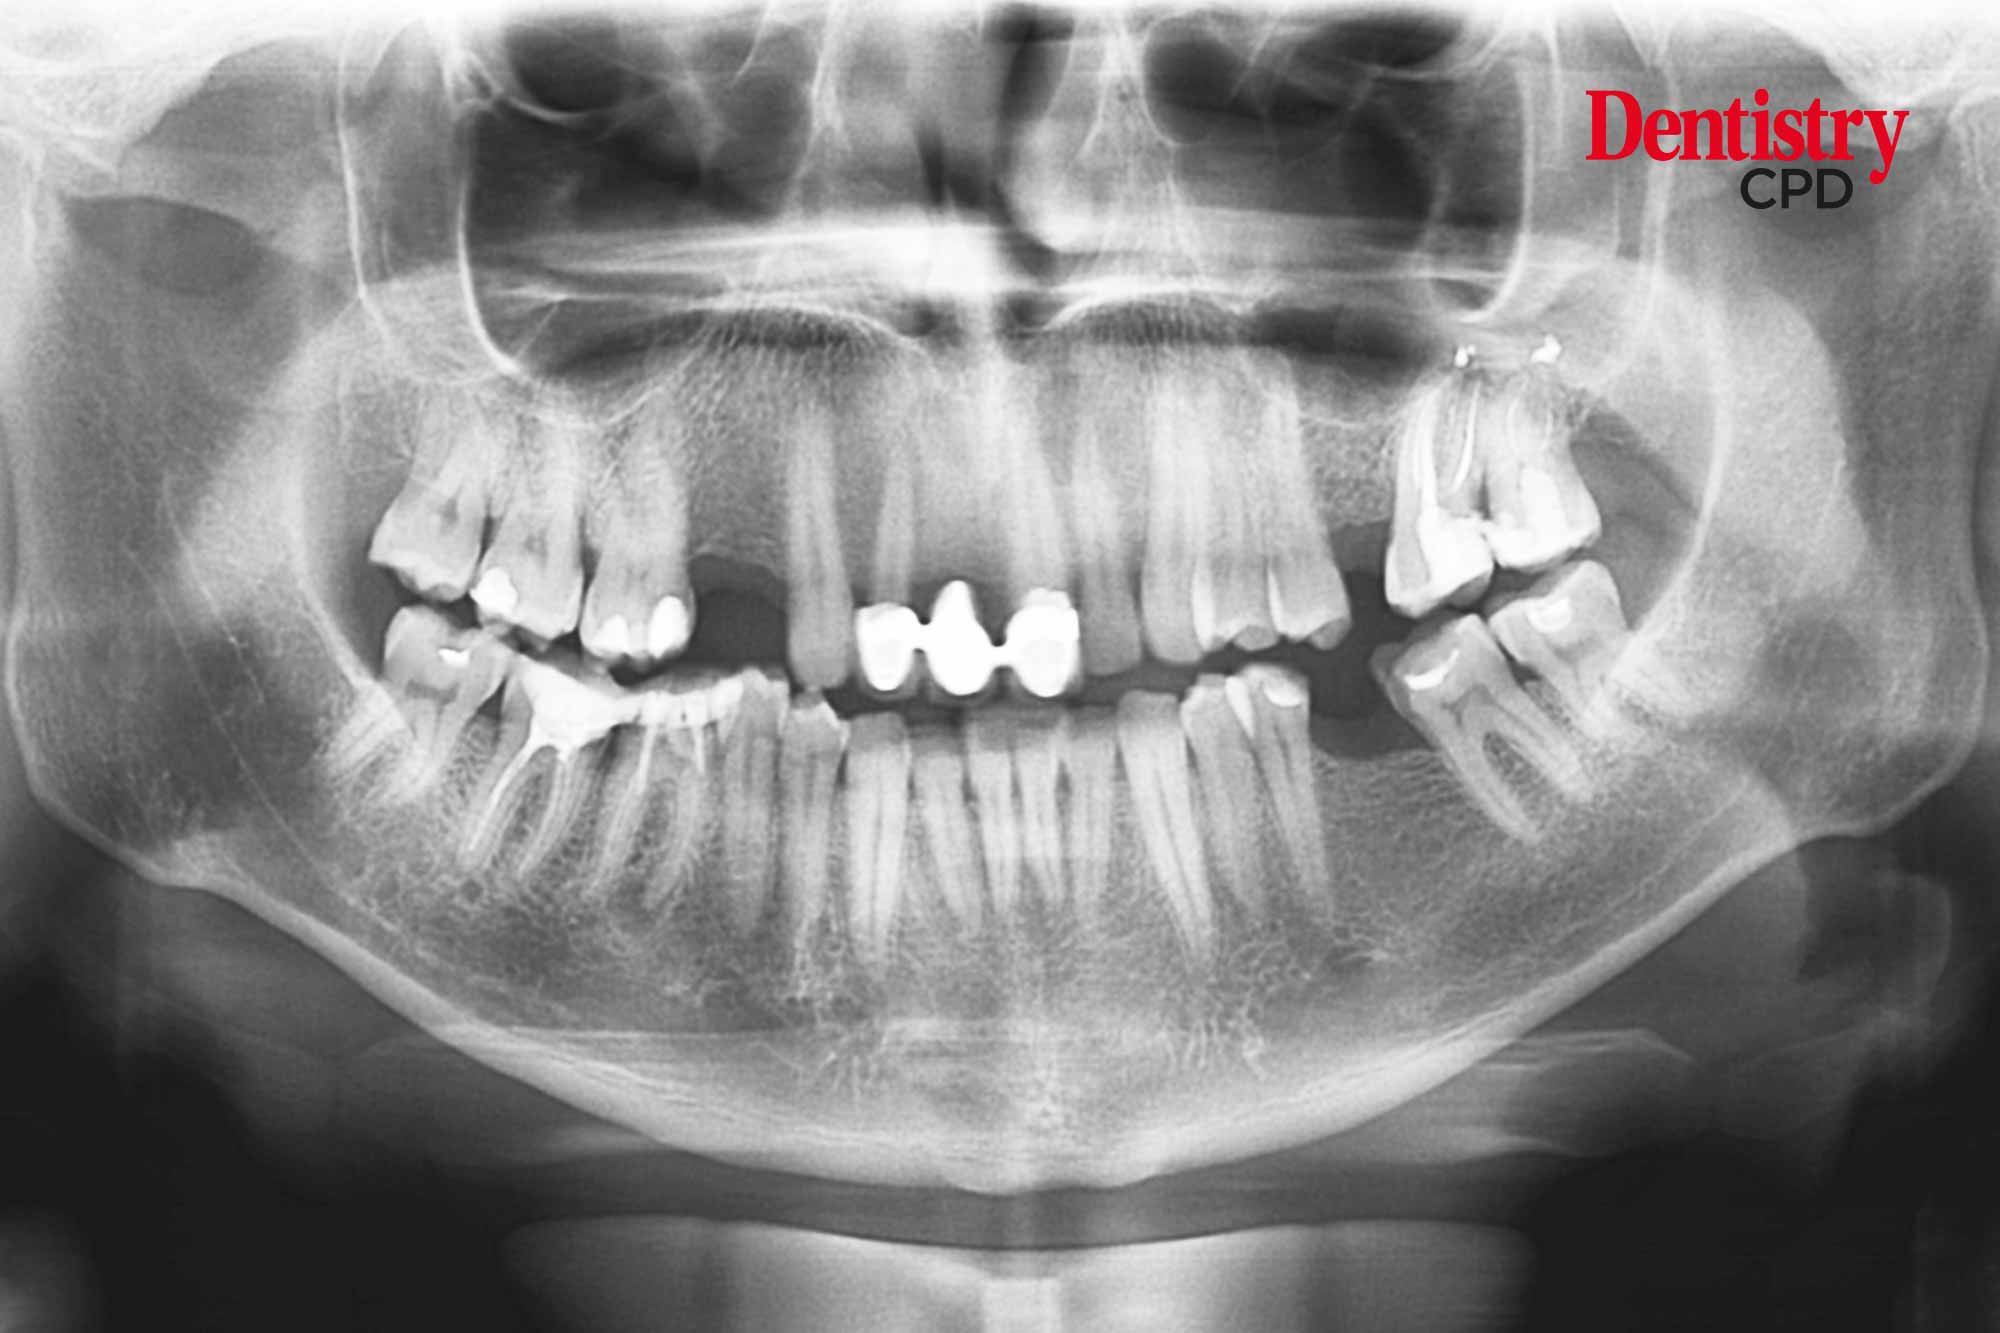

Radiography and radiation protection

Dental radiography: safe use of X-ray equipment

Stephen Green and Liam Sherar discuss the safe use of X-ray equipment and the changes and implications of the publication of the second edition of guidance notes for dental practitioners.

To discuss 2020 Guidance Notes for Dental Practitioners on the Safe Use of X-ray Equipment (2nd edition) and its implications to dental professionals.